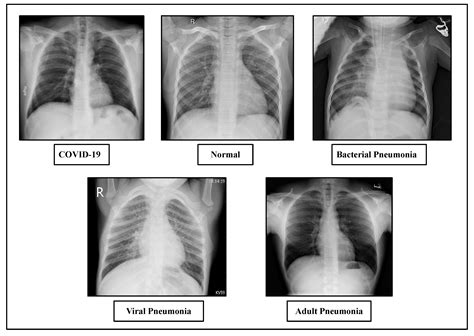

Healthy lungs appear mostly black on an X-ray because they are filled with air. When pneumonia is present, the areas of the lung affected by the infection appear as opaque, white, or cloudy patches. This phenomenon is known as consolidation. It occurs because the air in the alveoli has been displaced by fluid, inflammatory cells, or debris, which blocks the passage of X-rays.

Radiologists look for specific patterns of these opacities to better understand the nature of the infection:

• Lobar Pneumonia: This appears as a distinct area of consolidation restricted to one lobe of the lung. It is often associated with bacterial infections.

• Bronchopneumonia: This presents as patchy, diffuse opacities scattered throughout both lungs, rather than being confined to one area.

• Interstitial Pneumonia: Often caused by viral infections, this shows up as fine, lace-like markings or reticular patterns rather than dense consolidation.

• pneumonia lung x ray pictures

• severe pneumonia chest x ray

• x ray findings in pneumonia

• pneumonia on x ray pictures

• chest x rays for pneumonia

• chest x ray pneumonia picture